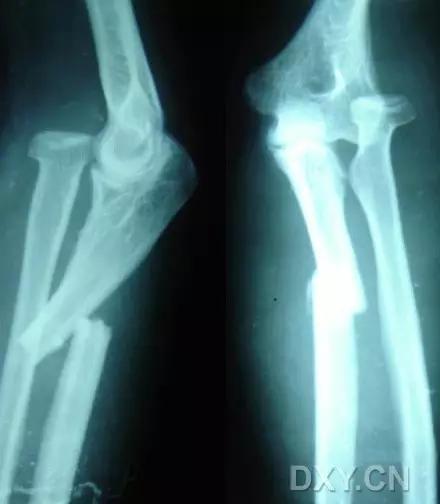

9. Monteggia 骨折(孟氏骨折)

尺骨近端 1/3 骨折合并桡骨头半脱位。

(来源:Radiopaedia)

成人 Monteggia 骨折

儿童 Monteggia 骨折

10. Galeazzi 骨折(盖氏骨折)

桡骨干下 1/3 骨折合并尺骨小头脱位。

盖氏骨折正侧位(来源:Orthobullets)